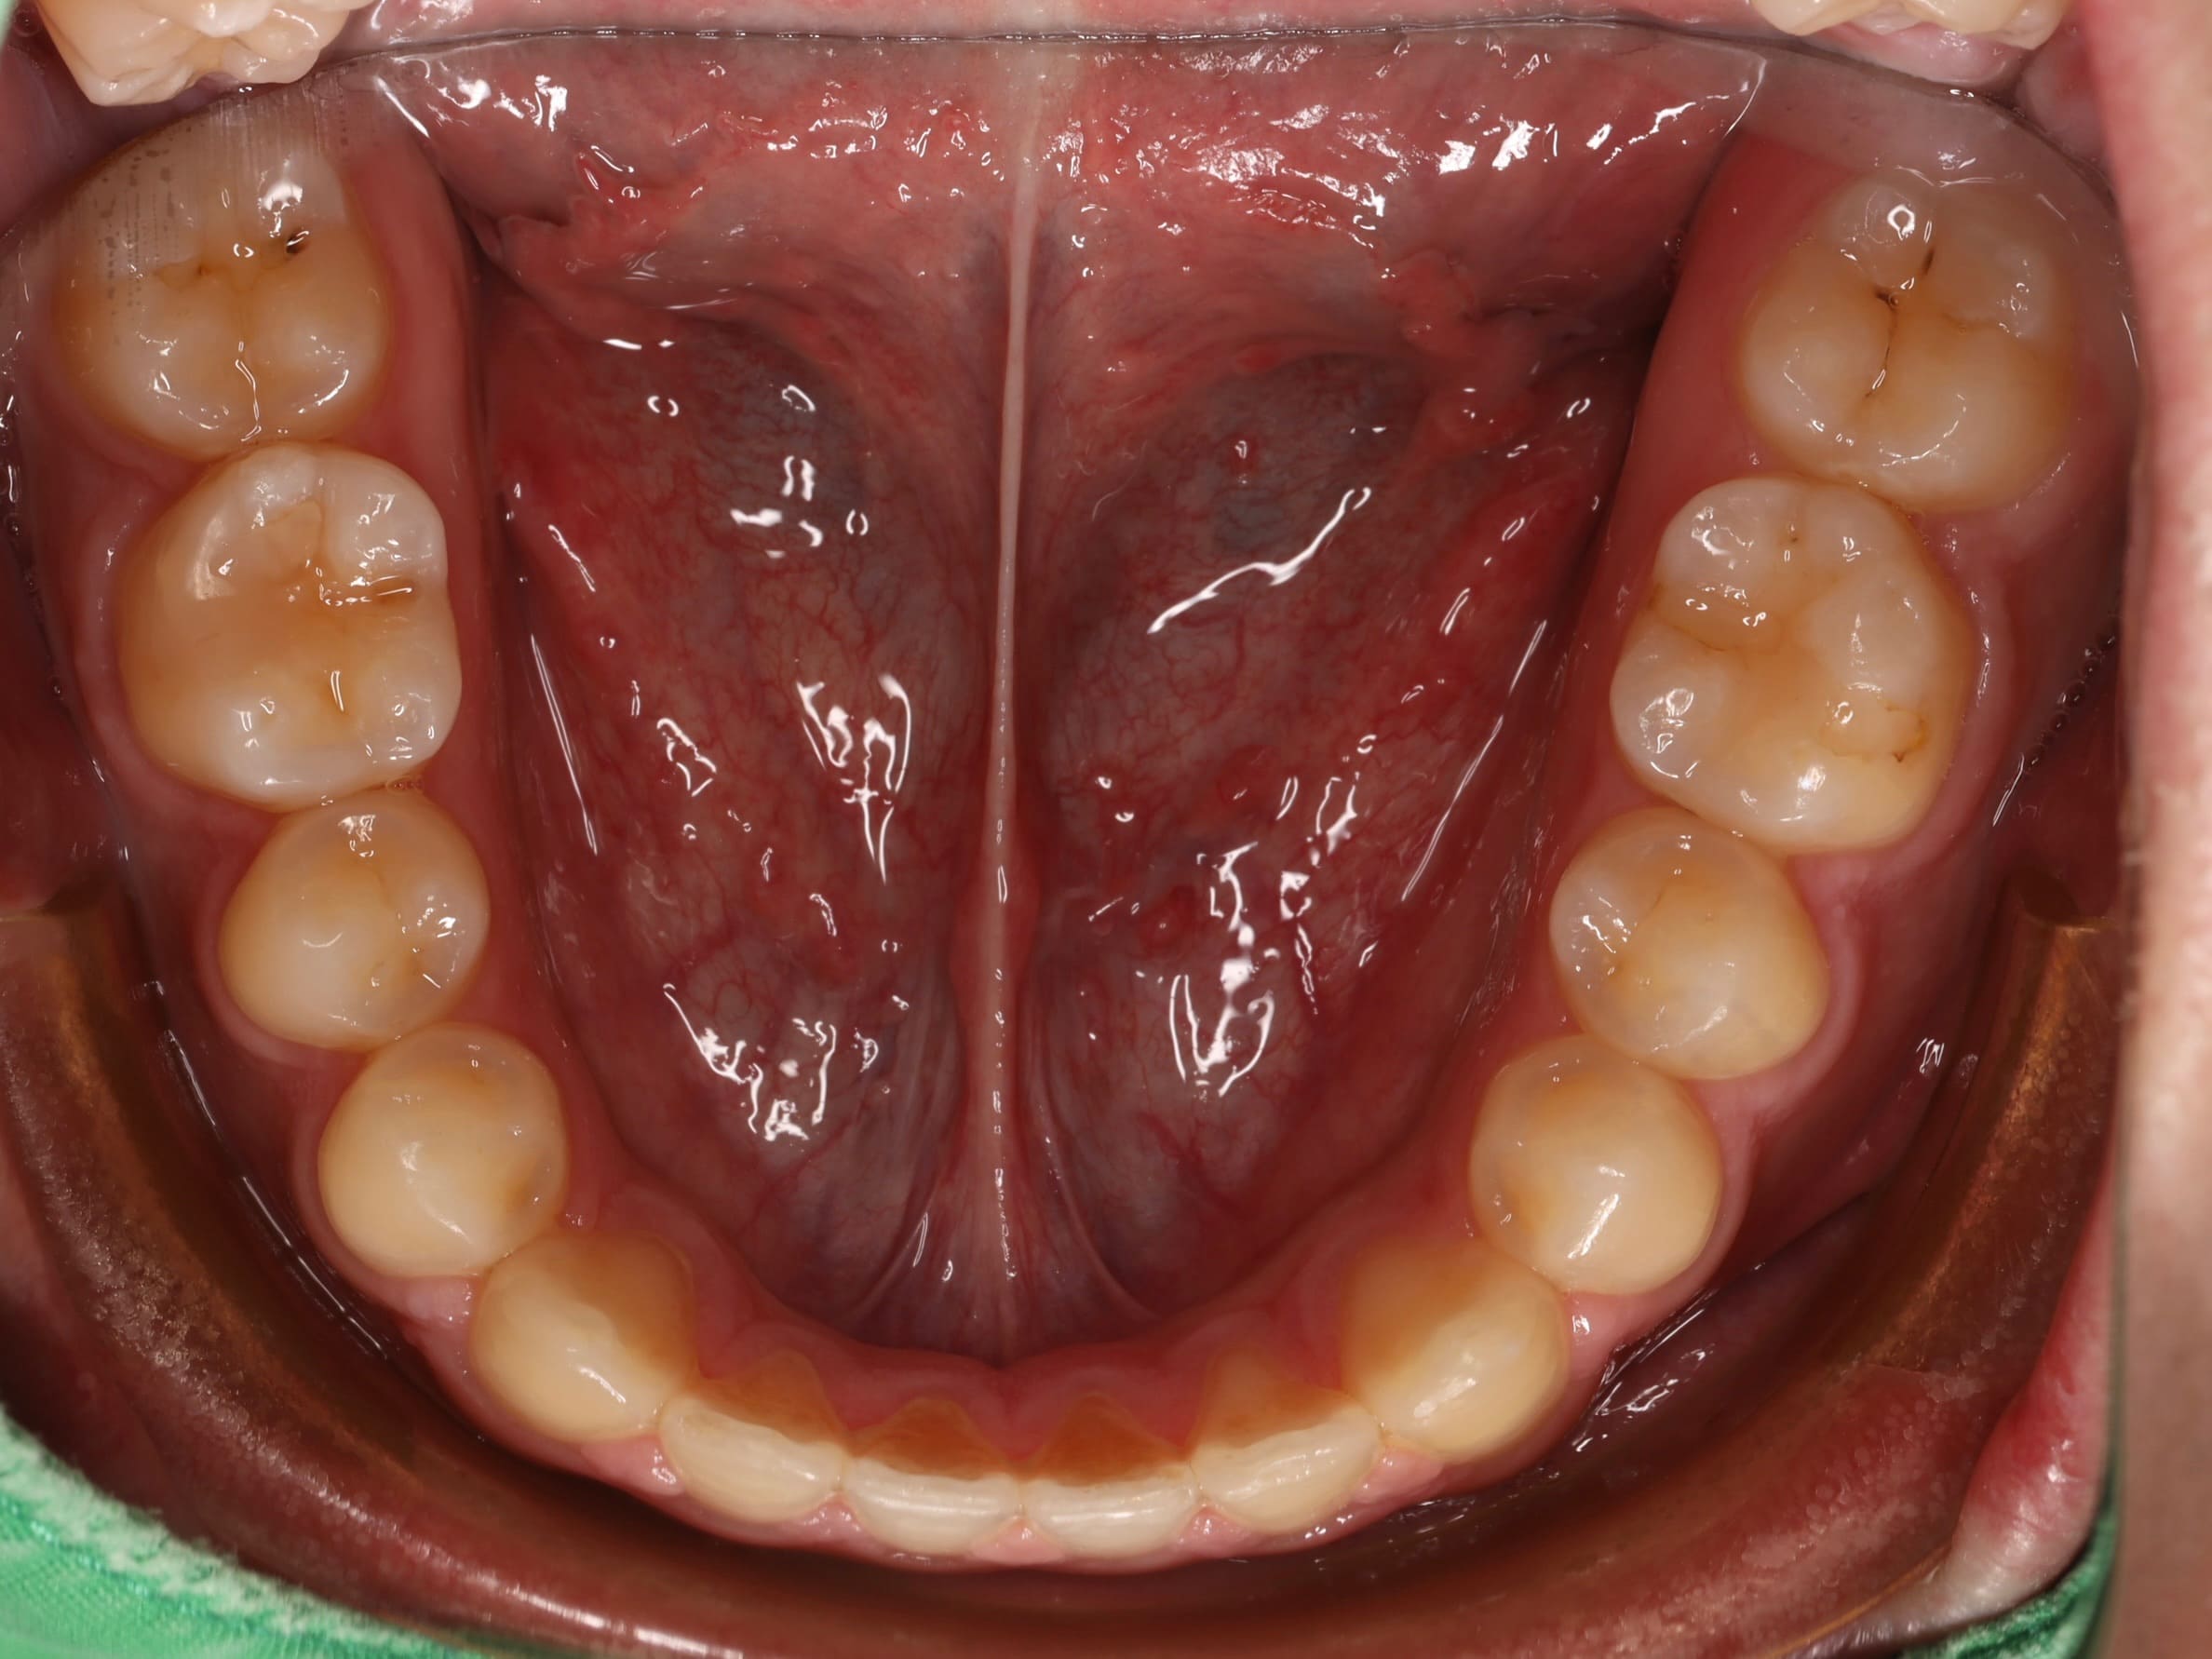

針對這些問題,我們擬定了完整的治療方案。首先,利用矯正的方式,將後方的第二大臼齒和智齒慢慢往前移動,填補缺牙的空間,同時調整上下排牙齒的咬合關係,讓錯咬的情況回復到正常的咬合狀態。當矯正治療完成後,病患的狀況其實已經改善了許多。

為了讓笑容更加完美,我們接著運用雷射方式進行微創的牙冠增長術,調整前牙美觀區牙齦的高度,讓牙齦和牙齒的比例更協調,整體笑容線條也更加自然。

完成所有療程後,病患的笑容真的煥然一新!不僅外觀上有了明顯的改變,整個人也變得更愛笑、更有自信了。